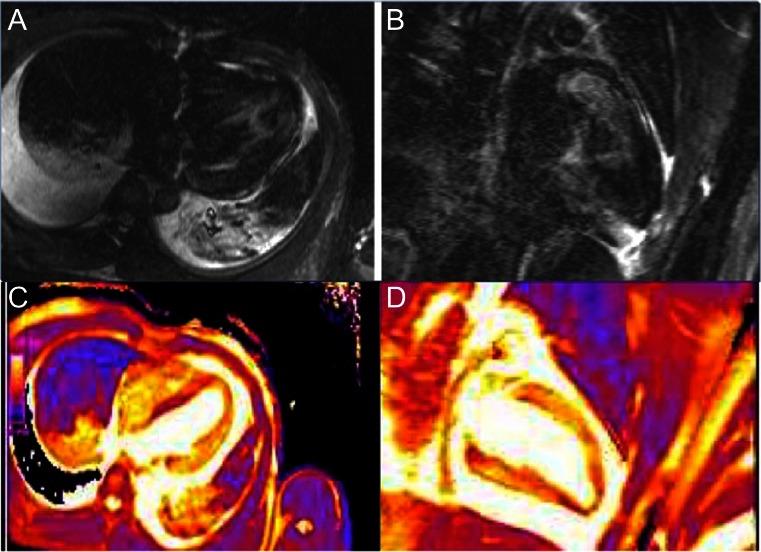

Acute coronary syndrome (ACS) still remains one of the leading causes of mortality and morbidity worldwide. Seven to fifteen percent of patients presenting with ACS have unobstructed coronary artery disease (CAD) on urgent angiography. Patients with ACS and unobstructed coronary arteries represent a clinical dilemma and their diagnosis and management is quite variable in current practice. Cardiovascular magnetic resonance imaging with its unique non-invasive myocardial tissue characterization property has the potential to identify underlying etiologies and reach a final diagnosis. These include acute and chronic myocarditis, embolic/spontaneous recanalization myocardial infarction, and Tako-Tsubo cardiomyopathy, and other conditions. Establishing a final diagnosis has a direct implication on patient's management and prognosis. In this article, we have reviewed the current evidence on the diagnostic role of cardiac magnetic resonance (CMR) in patients with ACS and unobstructed coronary arteries. We have also highlighted the potential role of CMR as a risk stratification or prognostication tool for this patient population.

急性冠状动脉综合征(ACS)仍是全球范围内导致死亡和发病的主要原因之一。7%至15%表现为ACS的患者在紧急血管造影时显示冠状动脉疾病(CAD)无阻塞。患有ACS且冠状动脉无阻塞的患者面临临床困境,目前其诊断和管理差异很大。心血管磁共振成像凭借其独特的非侵入性心肌组织特征特性,有潜力识别潜在病因并做出最终诊断。这些病因包括急性和慢性心肌炎、栓塞/自发再通心肌梗死、应激性心肌病以及其他病症。做出最终诊断对患者的管理和预后有直接影响。在本文中,我们回顾了关于心脏磁共振(CMR)在患有ACS且冠状动脉无阻塞患者中的诊断作用的当前证据。我们还强调了CMR作为该患者群体风险分层或预后评估工具的潜在作用。